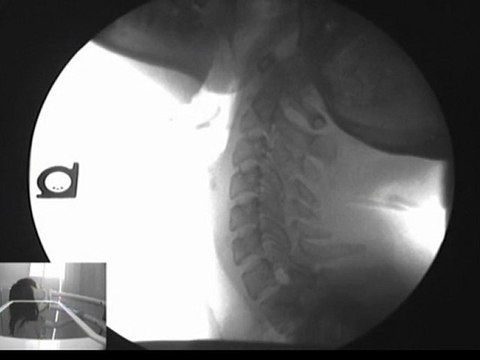

VancouverWashingtonChiropractor.org Get the free special report at our site, 20 Things You Must Know Before Choosing a Chiropractor in Vancouver, Washington!